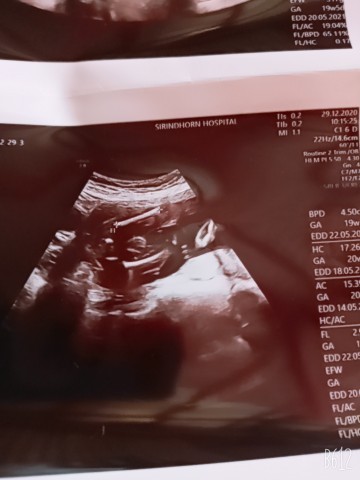

19+6จ้า